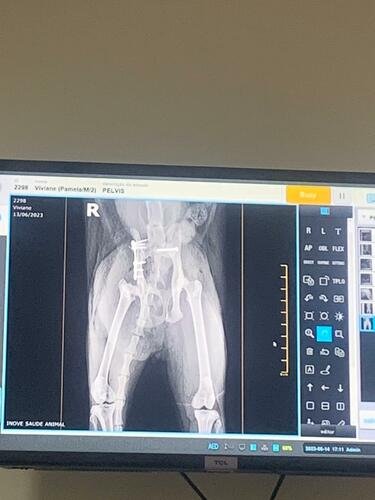

A indicação foi de imediata cirurgia e, vendo as dores e o perigo de infecção e hemorragia interna que ela corria, fora o desespero de nossa filha Clarice, que é extremante ligada à gatinha, assumimos esse compromisso, mesmo não conhecendo ainda os valores para cobrir todos os custos.

Pós-operatório (placa e parafusos):